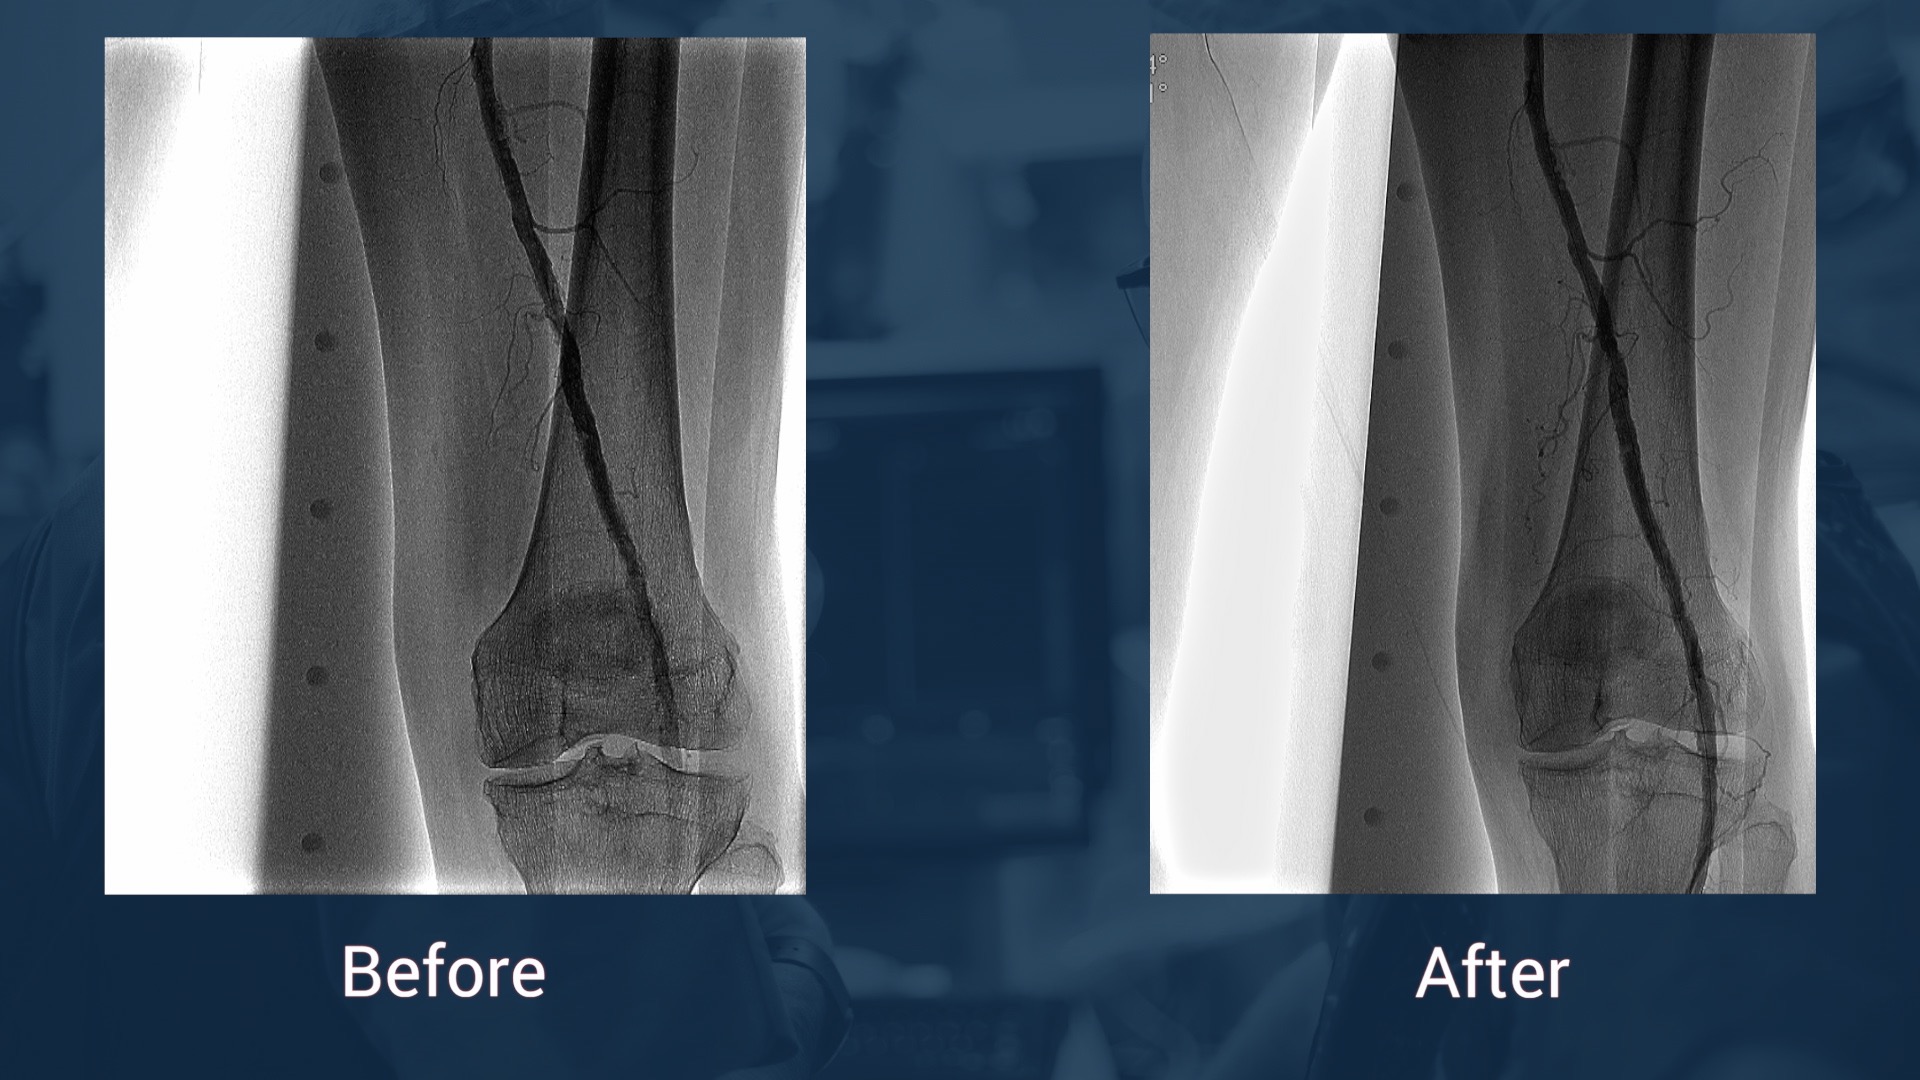

Clinical Data: Female, 79 years old

2014: Stenting left SFA + PTA left AP

Small non-healing ulcers left foot (Rutherford 5)

ISRO left SFA occlusion - occlusion of the native PA

Right SFA puncture – cross over

Recanalization

Vessel Prep

Ranger DCB – provisional stenting

Plan B: retrograde access ATA